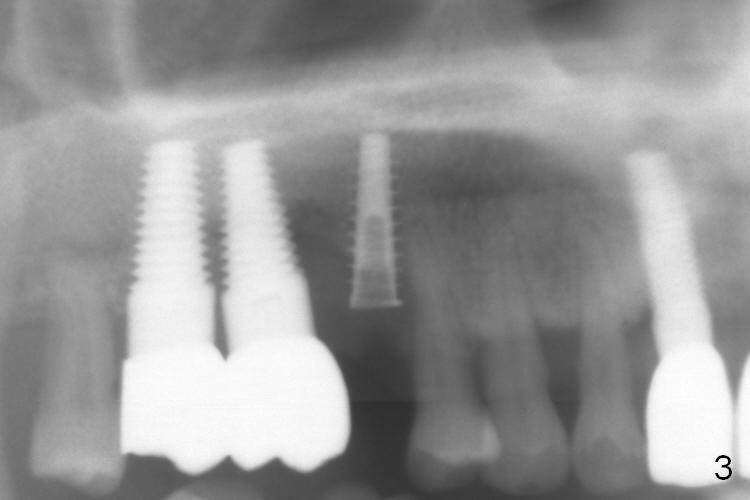

The distal buccal (Fig.1) and palatal (Fig.2) papillae (*) are recessive at the tooth #4. Following extraction and use of 3.8 mm Magic Drill, a 4.5x13 mm implant is placed lower than the mesial crest (Fig.3) to reduce the chance of the distal implant thread exposure. The latter is a measure to decrease peri-implantitis. A 4.5x5.7(4) mm pair abutment is placed (Fig.4,5). The remaining socket is filled with allograft/Osteogen placement. The large space between #3 and 4 implants is occupied by the healthy gingiva, where bone graft cannot get in.

The distal papilla reforms buccally (Fig.8 *) and palatally (Fig.9) 4 months postop. It appears that the 4 mm cuff of the pair abutment (Fig.10 >) is apical to the mesial crest (*). The distal coronal implant threads seem to be covered by bone graft (Fig.11 <). Therefore pair abutments with 5 mm or more cuff are required in cases of the uneven bone. Implants have to be placed deep. CT taken 3 months post cementation (10 months postop) shows that the implant is placed in the middle of the alveolus without apparent thread exposure. CT taken 1 year and 8 months post cementation (Fig.13) shows that the implant is placed in the middle of the alveolus without apparent thread exposure, as compared to those at #2 and 3, which are placed buccal (B).